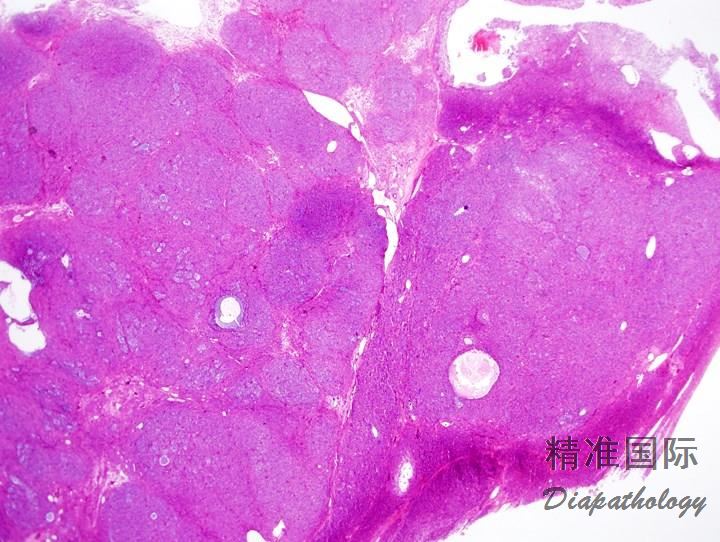

囊实性最常见,囊内可含有血性液体。也可为实性或完全囊性变;后者常为多房,罕见单房。实性区通常为黄褐色或灰白色,偶尔可见广泛的坏死和(或)出血

镜下典型表现为肿瘤细胞弥漫或结节状分布,其间穿插大小和形状不一的滤泡,但也可以是规则的圆形和卵圆形滤泡;